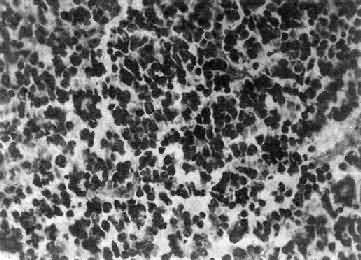

图16-23 星形胶质细胞瘤 左大脑半球肿胀,肿瘤边界不清,部分呈胶冻状 镜下,肿瘤细胞形态多样,可相似于纤维型星形胶质细胞、原浆型星形胶质细胞和肥胖星形胶质细胞,故分别称为纤维型、原浆型和肥胖型星形胶质细胞瘤。前二者为良性肿瘤,后者性质介于良恶性之间。如肿瘤细胞出现间变,细胞密度增大,异型性明显,核深染,出现核分裂像,毛细血管内皮细胞增生,则为间变性星形胶质细胞瘤,为恶性肿瘤。 高度恶性的星形胶质细胞瘤称为多形性胶质母细胞瘤(glioblastoma multiforme),多见于成人。肿瘤好发于额叶、颞叶白质,浸润范围广,常可穿过胼胝体到对侧,呈蝴蝶状生长(图16-24)。瘤体因常有出血坏死而呈红褐色。镜下,细胞密集,异型性明显,可见怪异的单核或多核瘤巨细胞。出血坏死明显,是其区别于间变性星形胶质细胞瘤的特征。毛细血管明显增生,内皮细胞增生、肿大,可导致管腔闭塞和血栓形成。肿瘤发展迅速,预后极差,患者多在2年内死亡。